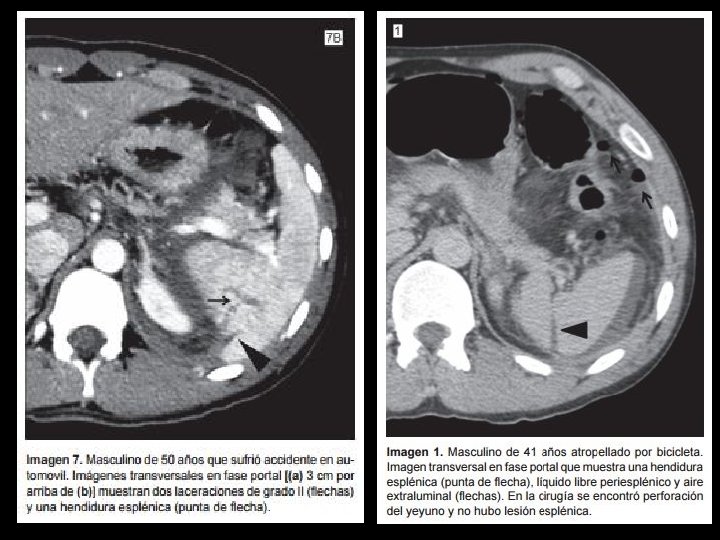

DIAGNOSTICO DIFERENCIAL Hendidura Laceración • Bordes lisos, redondeados • Fase tardía no cambian apariencia

DIAGNOSTICO DIFERENCIAL Hendidura Laceración • Bordes lisos, redondeados • Fase tardía no cambian apariencia • Pueden tener grasa en su interior • Bordes irregulares • Fase tardía se homogeneizan con resto de bazo